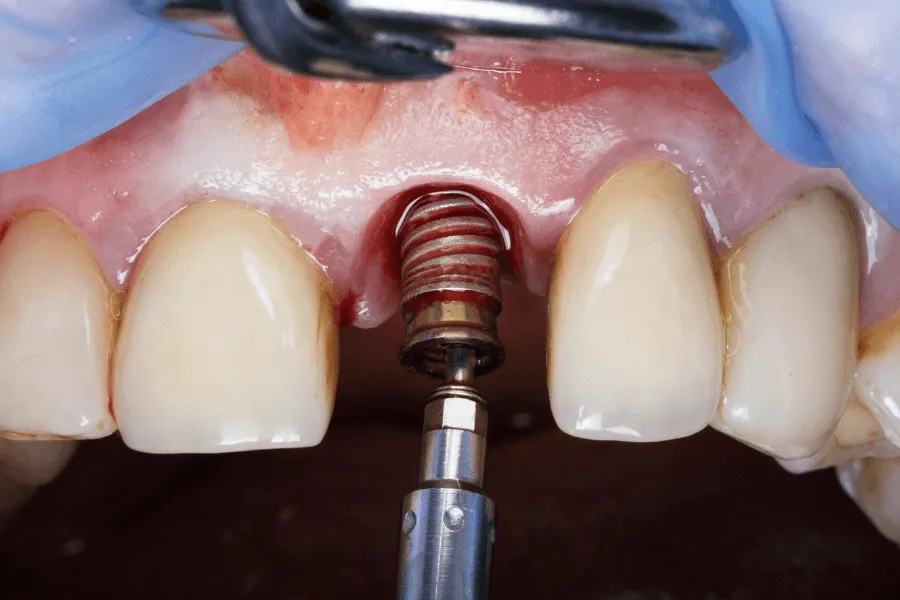

Profesjonalne oczyszczenie implantów

To pierwszy i najważniejszy etap terapii. Biofilm bakteryjny nie jest możliwy do usunięcia samą szczoteczką - potrzebne są specjalistyczne narzędzia:

Ultradźwięki dedykowane implantom

Skalery stosowane przy implantach mają specjalne końcówki wykonane z materiałów, które nie rysują powierzchni tytanu.

Pozwalają na:

• oczyszczenie gwintu implantu

• usunięcie twardych złogów

• likwidację biofilmu w trudno dostępnych miejscach

Już samo dokładne oczyszczenie często znacząco redukuje objawy zapalenia.